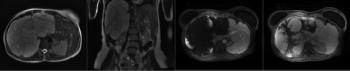

A 63-year-old man with NET metastatic to the liver undergoes MRI for evaluation of response to therapy. Based on the imaging, what is your diagnosis?